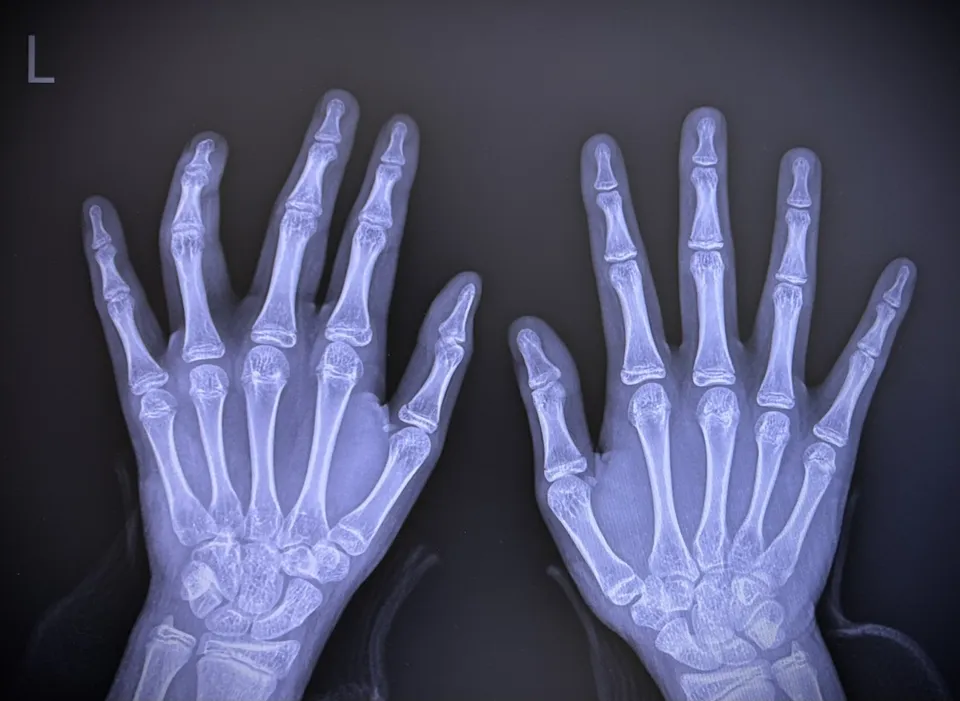

ズバリ回答!指をポキポキ鳴らすと「指が太くなる」って本当なの?

結論から言ってしまうと、この噂は「半分嘘で、半分本当」なんです。

正確に言うと、「骨自体が成長して太くなることはないけれど、関節周りが腫れて太く見えるようになる可能性は高い」というのが、私たち専門家の見解です。

医学的には「骨は太くならない」が正解!でも油断は禁物?

指をポキポキ鳴らしたからといって、骨が急に成長したり、骨の形がボコッと変わったりするという医学的な証拠はありません。

太く見えてしまうのは「炎症」や「組織の肥厚」が原因かも

骨そのものは太くなりませんが、「関節を守っている周りの組織」は別です。

指の関節を無理に引っ張ったり曲げたりして鳴らす行為は、関節を包んでいる「関節包(かんせつほう)」や「靭帯(じんたい)」に、瞬間的に強い負担をかけています。

つまり、骨が太くなったのではなく、「皮や肉が厚くなって、節(ふし)が太く見えてしまっている」状態と言えます。

指輪が入りにくくなったり、指のシルエットがゴツゴツしたりするのは、この「組織の変化」が原因のことが多いんですよ。